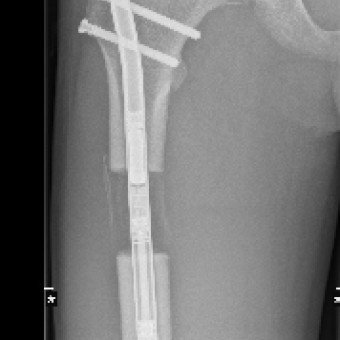

Die Knochenverlängerung mit dem magnetgetriebenen Marknagel Precice® hat sich als bedeutendste technologische Innovation in der Extremitätenrekonstruktion etabliert. Bei dieser Methode wird der getrennte Knochen durch Callusdistraktion täglich um etwa 1 mm verlängert. Im Vergleich zu externen Fixateuren ist diese vollimplantierte Lösung für Patientinnen und Patienten deutlich angenehmer und weniger schmerzhaft.

Die Ergebnisse sind ausgezeichnet und Komplikationen selten. Im schweizerischen Vergleich gehören wir auf diesem Gebiet zu den führenden Kliniken.